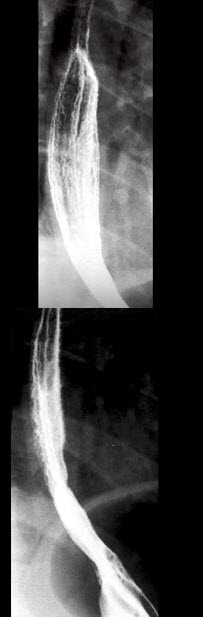

男,34岁,胸骨后烧灼痛1周,伴吞咽痛,餐后平卧时加剧,食管钡餐检查如图,最可能的诊断是()

男,34岁,胸骨后烧灼痛1周,伴吞咽痛,餐后平卧时加剧,食管钡餐检查如图,最可能